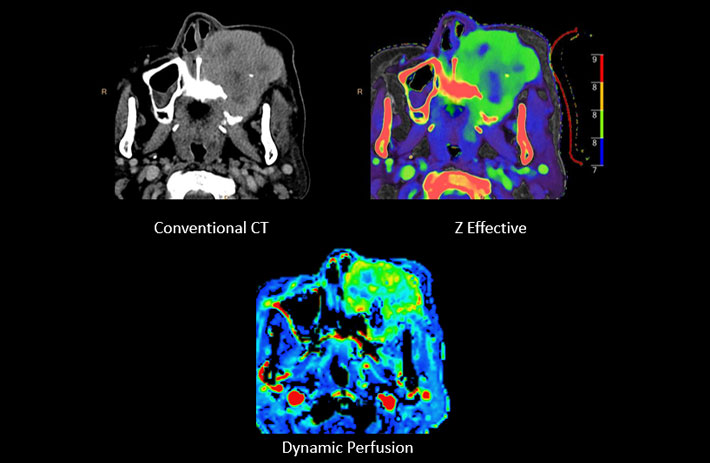

Mit dem Spektral-Detektor-CT werden Spektraldaten automatisch bei jedem Scan erfasst. Die Informationen stehen jederzeit auf der Scankonsole, der CT-Workstation sowie an jedem PACS-Arbeitsplatz zur Verfügung, sodass es nicht notwendig ist, den Patienten erneut zu scannen, bspw. wenn initial zufällige Anomalien festgestellt wurden. Dadurch profitieren Anwender durch eine höhere Diagnosesicherheit und weniger Nachuntersuchungen auf anderen bildgebenden Systemen. Unsere Fallsammlung zeigt, welchen klinischen Mehrwert der Spektral-Detektor-CT in unterschiedlichsten Anwendungsbereichen in der klinischen Routine bringt. Jede Woche gehen neue Fälle live.